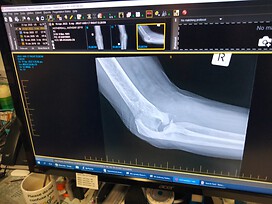

Shortly after I asked a surgeon to scrape and clean my elbows as they were getting painful. The surgeon brought up the scan and actually laughed ‘what’s wrong’ I asked, ‘you have no joints left to scrape and clean’, so that stuffed that idea and I’ve been living without elbow joints ever since. A little while ago I asked my GP what the bone was sticking out the back of my arm above my elbow 'that's the olecranon, but its not supposed to be there' was his answer.